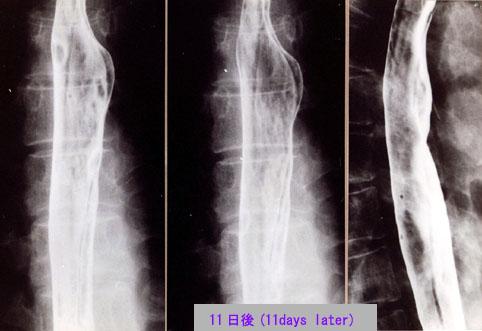

A case of idiopathic intramural hematoma of the esophagus diagnosed based on a natural history by X-ray and endoscopy.

Tokyo Pref., Cooperative study between National Cancer Center and Kyushu Cancer Center

[ Image ID:2690 ]

Inflammatory or ulcerative disease / lesions/Others

Esophagus/More than one of the above

X-ray

40 -